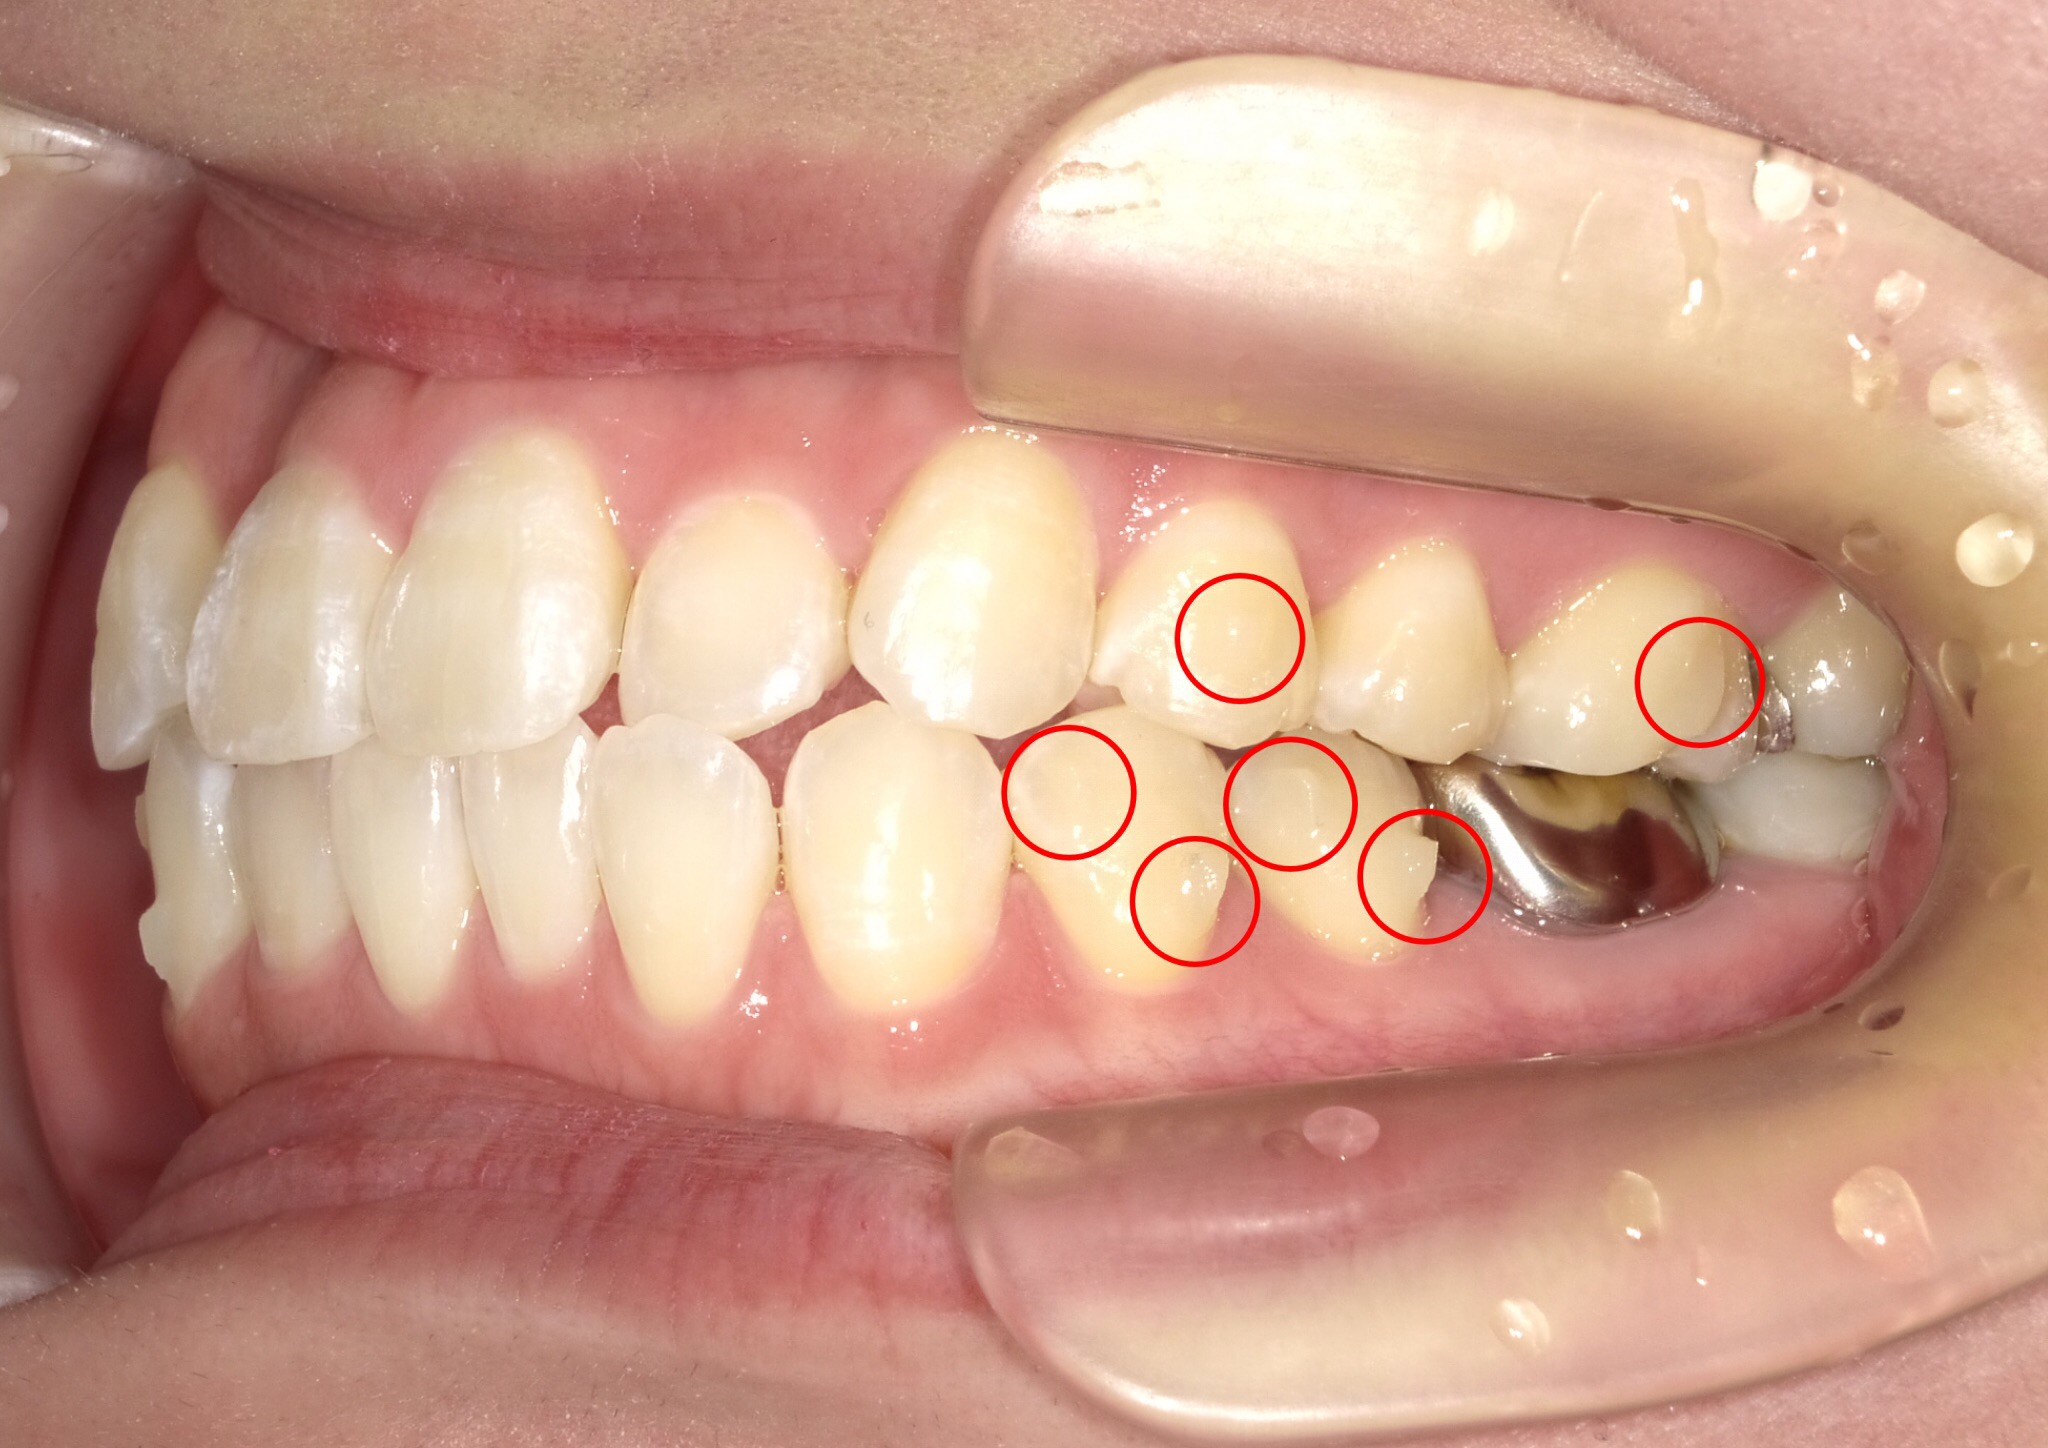

透明に近い、あるいは歯と同系色の『突起』のことをいいます。

↑写真でもあまり分からないくらいなので、目立ちません。